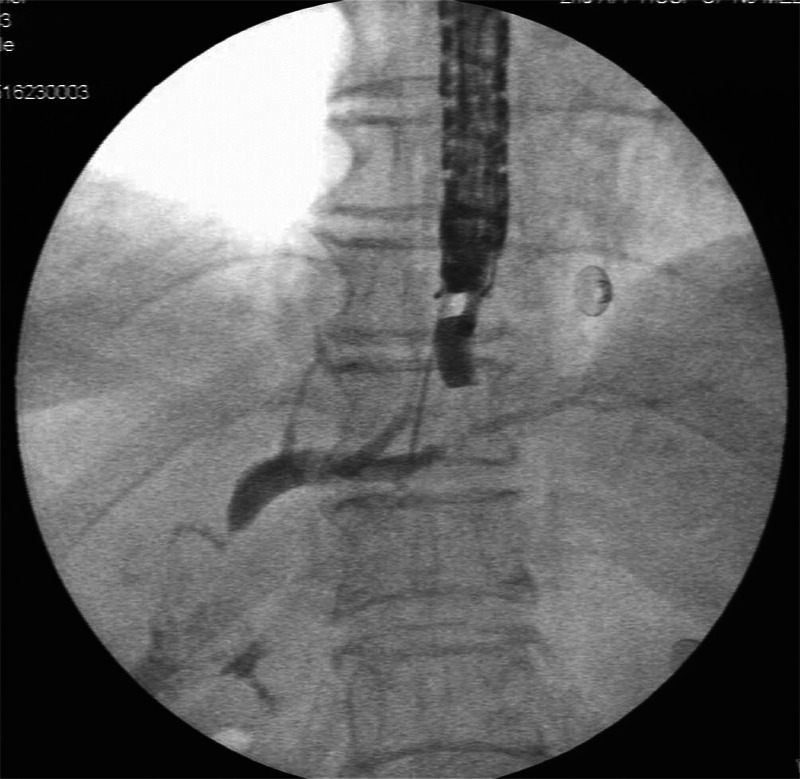

Guidewire technique and nasobiliary duct-assisted secondary EUS-guided biliary drainage.

导丝技术和鼻胆管辅助二次 EUS 引导胆道引流。